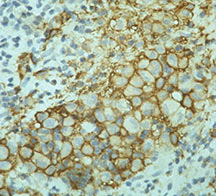

- Langerhans cell is diagnostic and clonal proliferation

- Nuclei show prominent nuclear groove (coffee-bean)

- Also composed of eosinophils and other inflammatory cells (non diagnostic component)

- Ratio of inflammatory cells to Langerhans cells varies

- Vimentin, CD1 and S-100 positivity